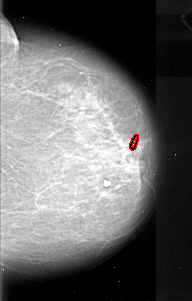

A_1081_1.RIGHT_CC

RIGHT_CC LINES 5416 PIXELS_PER_LINE 3451 BITS_PER_PIXEL 16 RESOLUTION 42 OVERLAY

FILE: A_1081_1.RIGHT_CC.OVERLAY

TOTAL_ABNORMALITIES 1

ABNORMALITY 1

LESION_TYPE CALCIFICATION TYPE PLEOMORPHIC DISTRIBUTION LINEAR

ASSESSMENT 4

SUBTLETY 4

PATHOLOGY MALIGNANT

TOTAL_OUTLINES 1

BOUNDARY